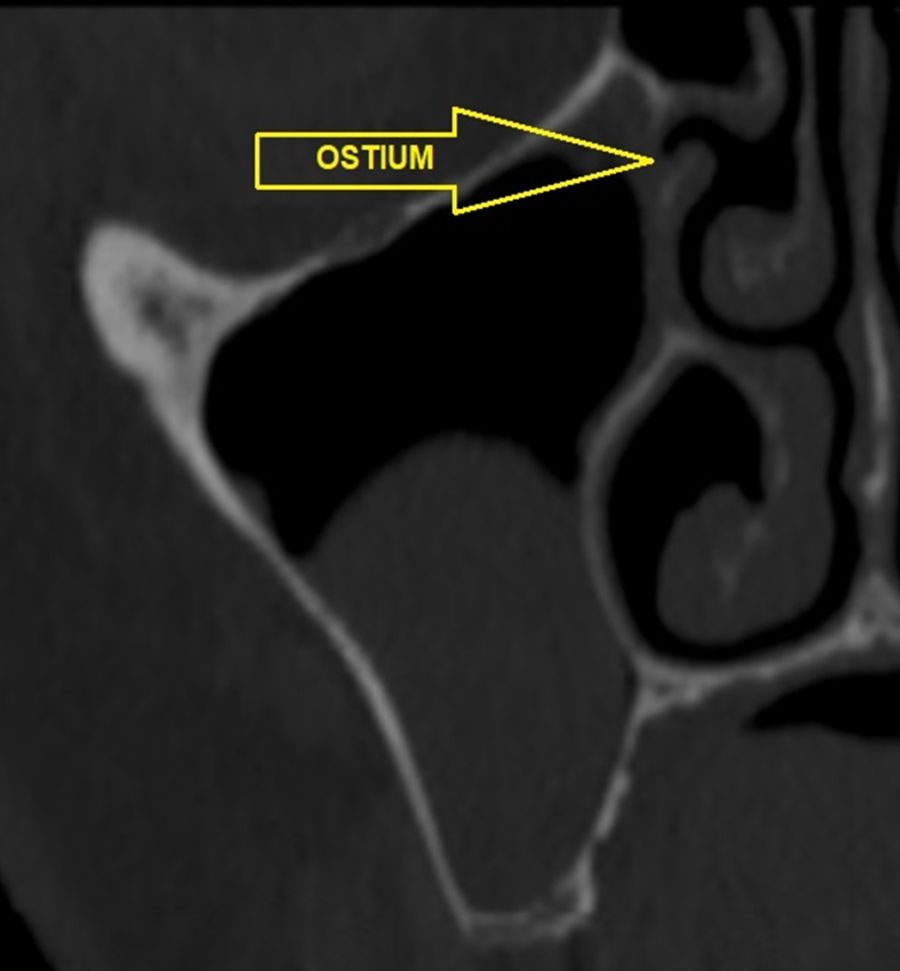

En la exploración radiográfica mediante escáner se apreció una lesión apical de pequeño tamaño en el 1.4 y una escasa disponibilidad ósea. Además, se observó imagen radioopaca cupuliforme de 3 x 2,8 cm en el seno maxilar derecho, compatible con un pseudoquiste sinusal (Figura 2). La extensión craneal alcanzaba la mitad superior del seno maxilar y el volumen de la lesión (5 cm³) era aproximadamente ⅓ del volumen sinusal (Figuras 3 y 4).